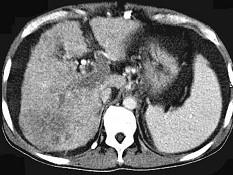

问题 女性,50岁,曾患乙型肝炎,肝硬化多年,右上腹胀痛1月余,CT检查如图所示,最全面的诊断是 ( )

选项 A.肝硬化、腹水伴胆管细胞癌 B.肝硬化、腹水伴原发性肝癌 C.肝硬化、腹水、肝癌并门脉癌栓 D.肝硬化、腹水并肝脓肿 E.肝硬化、腹水并肝血管瘤

答案 C